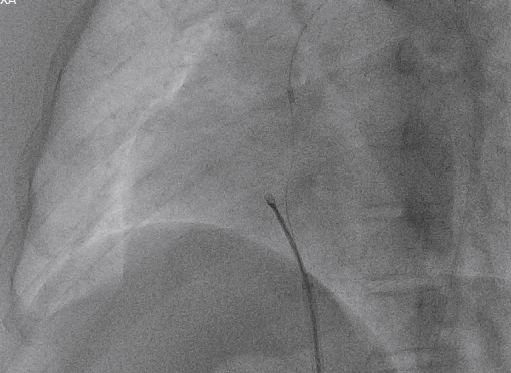

导丝通过主动脉窦瘤破口(左);导丝置于下腔静脉(右)

圈套器抓取导丝建立完整轨道